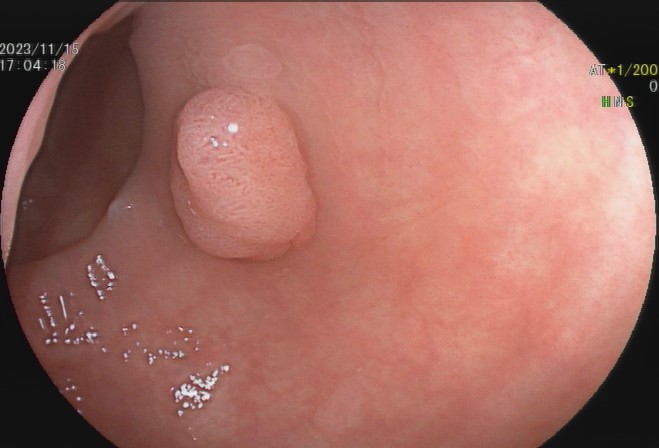

肠息肉是指突出于肠腔表面的隆起,在没有确定病理性质前统称为息肉,其发生率通常随年龄增加逐渐上升,病变部位以结直肠多发,与结直肠癌的发病有密切关系。

少数患者会发生便血,而结肠息肉很多的患者也可能会发生腹泻、黏液便、腹痛等症状,但这些症状无特异性,因此要确诊结肠息肉主要依赖结肠镜等检查,多数患者是在体检或因其他疾病做结肠镜时才被发现。

95%以上的结肠癌是从结肠息肉一步步转变而来,因此,结肠息肉一旦发现应该及时切除。发现息肉和早期肠癌,在内镜下就可以把这颗“定时炸弹”切除,创伤也小,对预期寿命几乎没有影响。